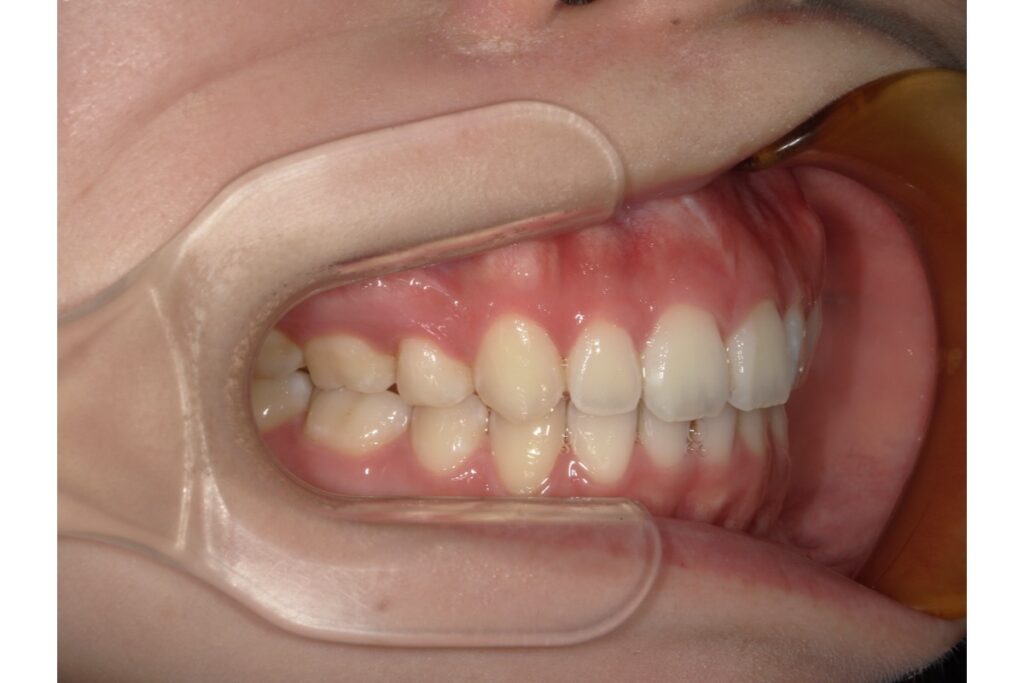

下記写真は初診時のものになります ↓

前歯を引っ込めたいという主訴だったので、抜歯をしての治療をすることになりました。インビザラインでは、歯を抜いての治療にも対応しております。歯を抜いた後、その隙間を使用して前歯を中に入れていきます!

歯を抜いて治療を行っているので、横から見たときの変化がとても分かりやすいかと思います。歯だけではなく、横顔も口元がスッキリしますよ。